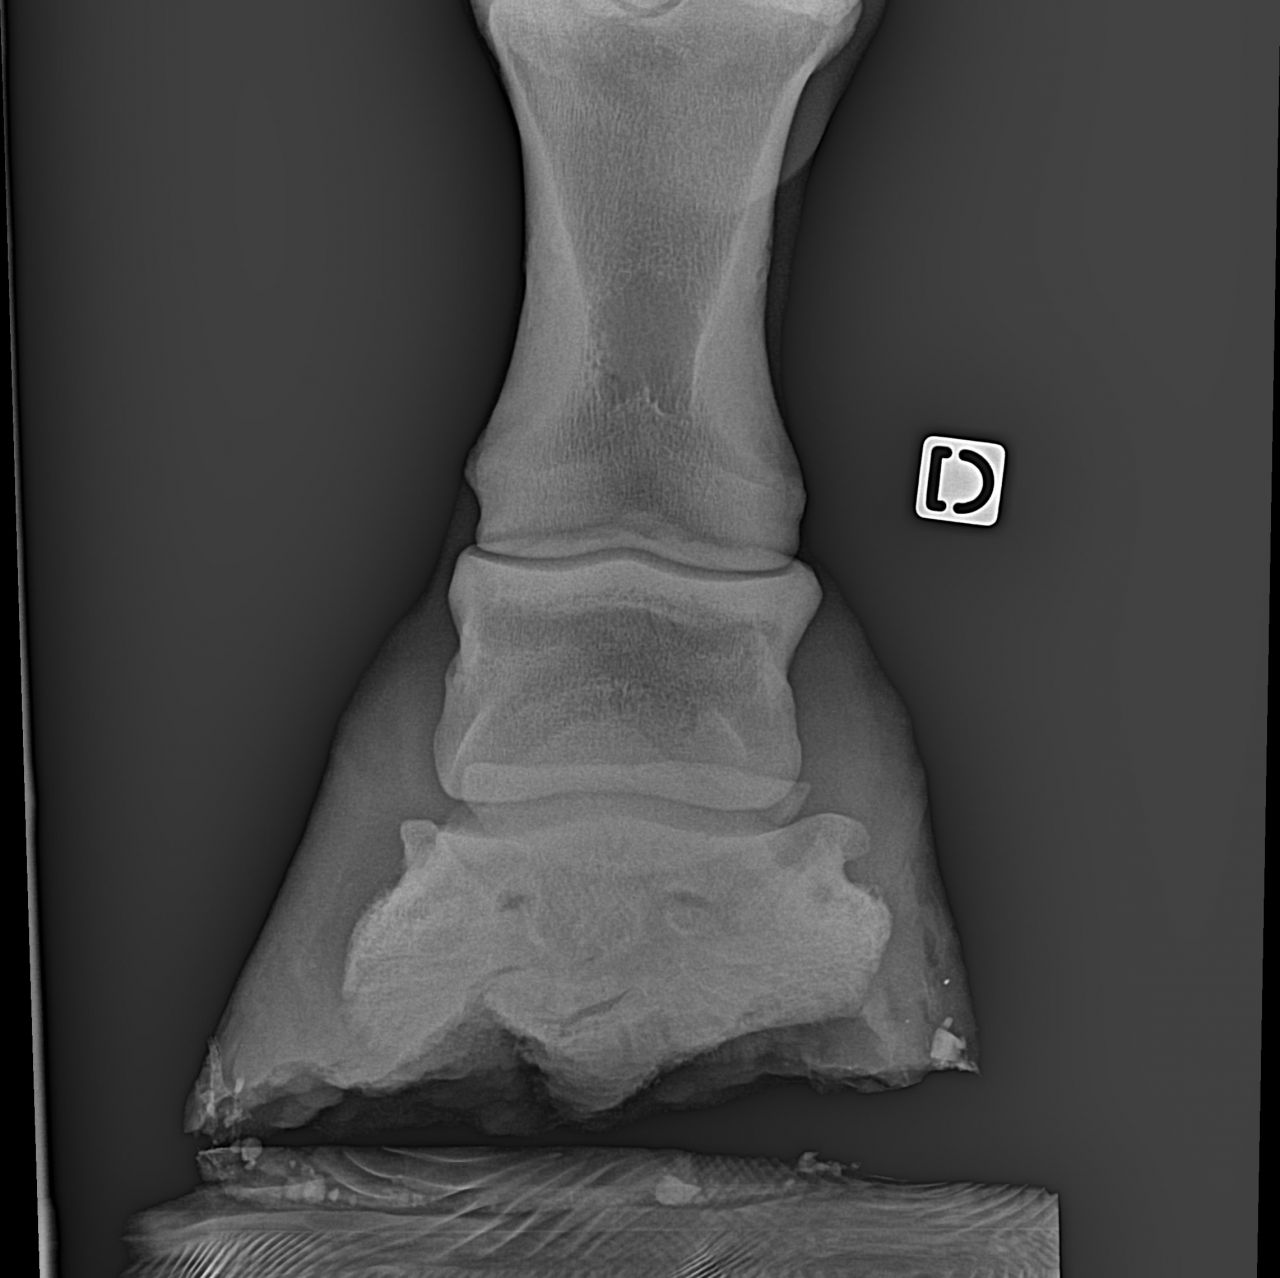

| Dire merci | les premières radios sont de juillet 2012 Voici les radios de l'antérieur droit fin septembre 2012 ![]() et celles de l'antérieur gauche ![]() ![]() |

Déconnecté | ben oui en voyant les radios, je me suis dit ostéïte direct. d'ailleurs elles sont assez impressionnantes. l'ostéïte a un caractère assez definitif,l'os ne peux pas se reminéraliser. les anti inflammatoires, c'est pour eviter qu'il y a ai une nouvelle infection qui déminéralise encore plus. quant à le remonter ....vu tes radios ... il faut imaginer que ses phalanges sont devenues aussi légère que de la roche volcanique pleine de trous ... au moindre choc, il va souffrir, et il risque des fissures de fatigue et de traumatisme aussi ... franchement, tes radios sont pas très encourageantes :S |

| Dire merci | j'ai eu le spécialiste au telephone... Alors mon cheval sera remontable sans problème par la suite. La je dois lui refaire une écho du pied, j'ai téléphoné au spécialiste B... Et m'envoie à dijon, j'attends de savoir si ils peuvent me faire l'échos. Le cheval n'avait pas qu'une ostéite mais aussi un soucis au tendon du à l'abaissement des talons suite au parage naturel... Donc avec l'échos, on va voir si c'est l'os ou el tendon le plus touché. Si c'ets l'os on fera une injection de tildren si c'est le ligament, j'aurai un autre produit. |